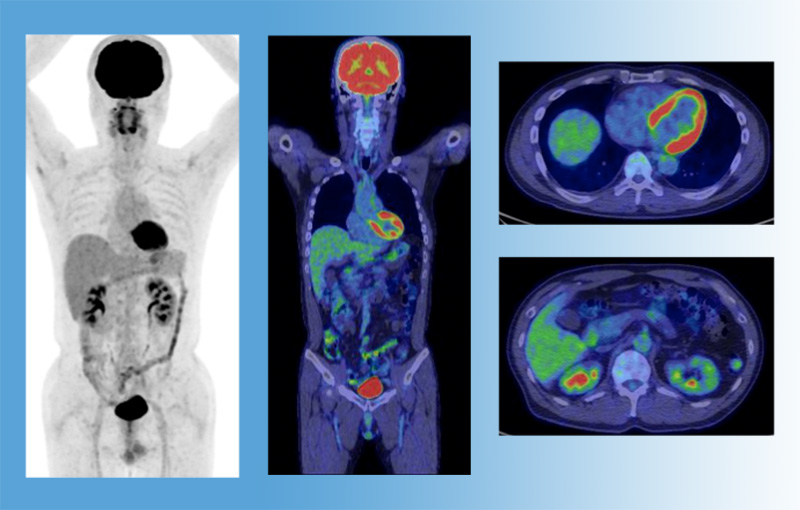

がん医療

2人にひとりは罹るといわれている「がん」ですが、要因として高齢化、生活習慣等があげられています。松阪中央総合病院、鈴鹿中央総合病院は「地域がん診療連携拠点病院」、三重北医療センターいなべ総合病院は「三重県がん診療連携病院」の指定を受け、高度治療・診断機器を活用した手術・化学療法・放射線治療等の集学的治療、緩和ケアにいたるがん医療を提供しています。

高度医療機器の保有台数

PET-CT1台 |